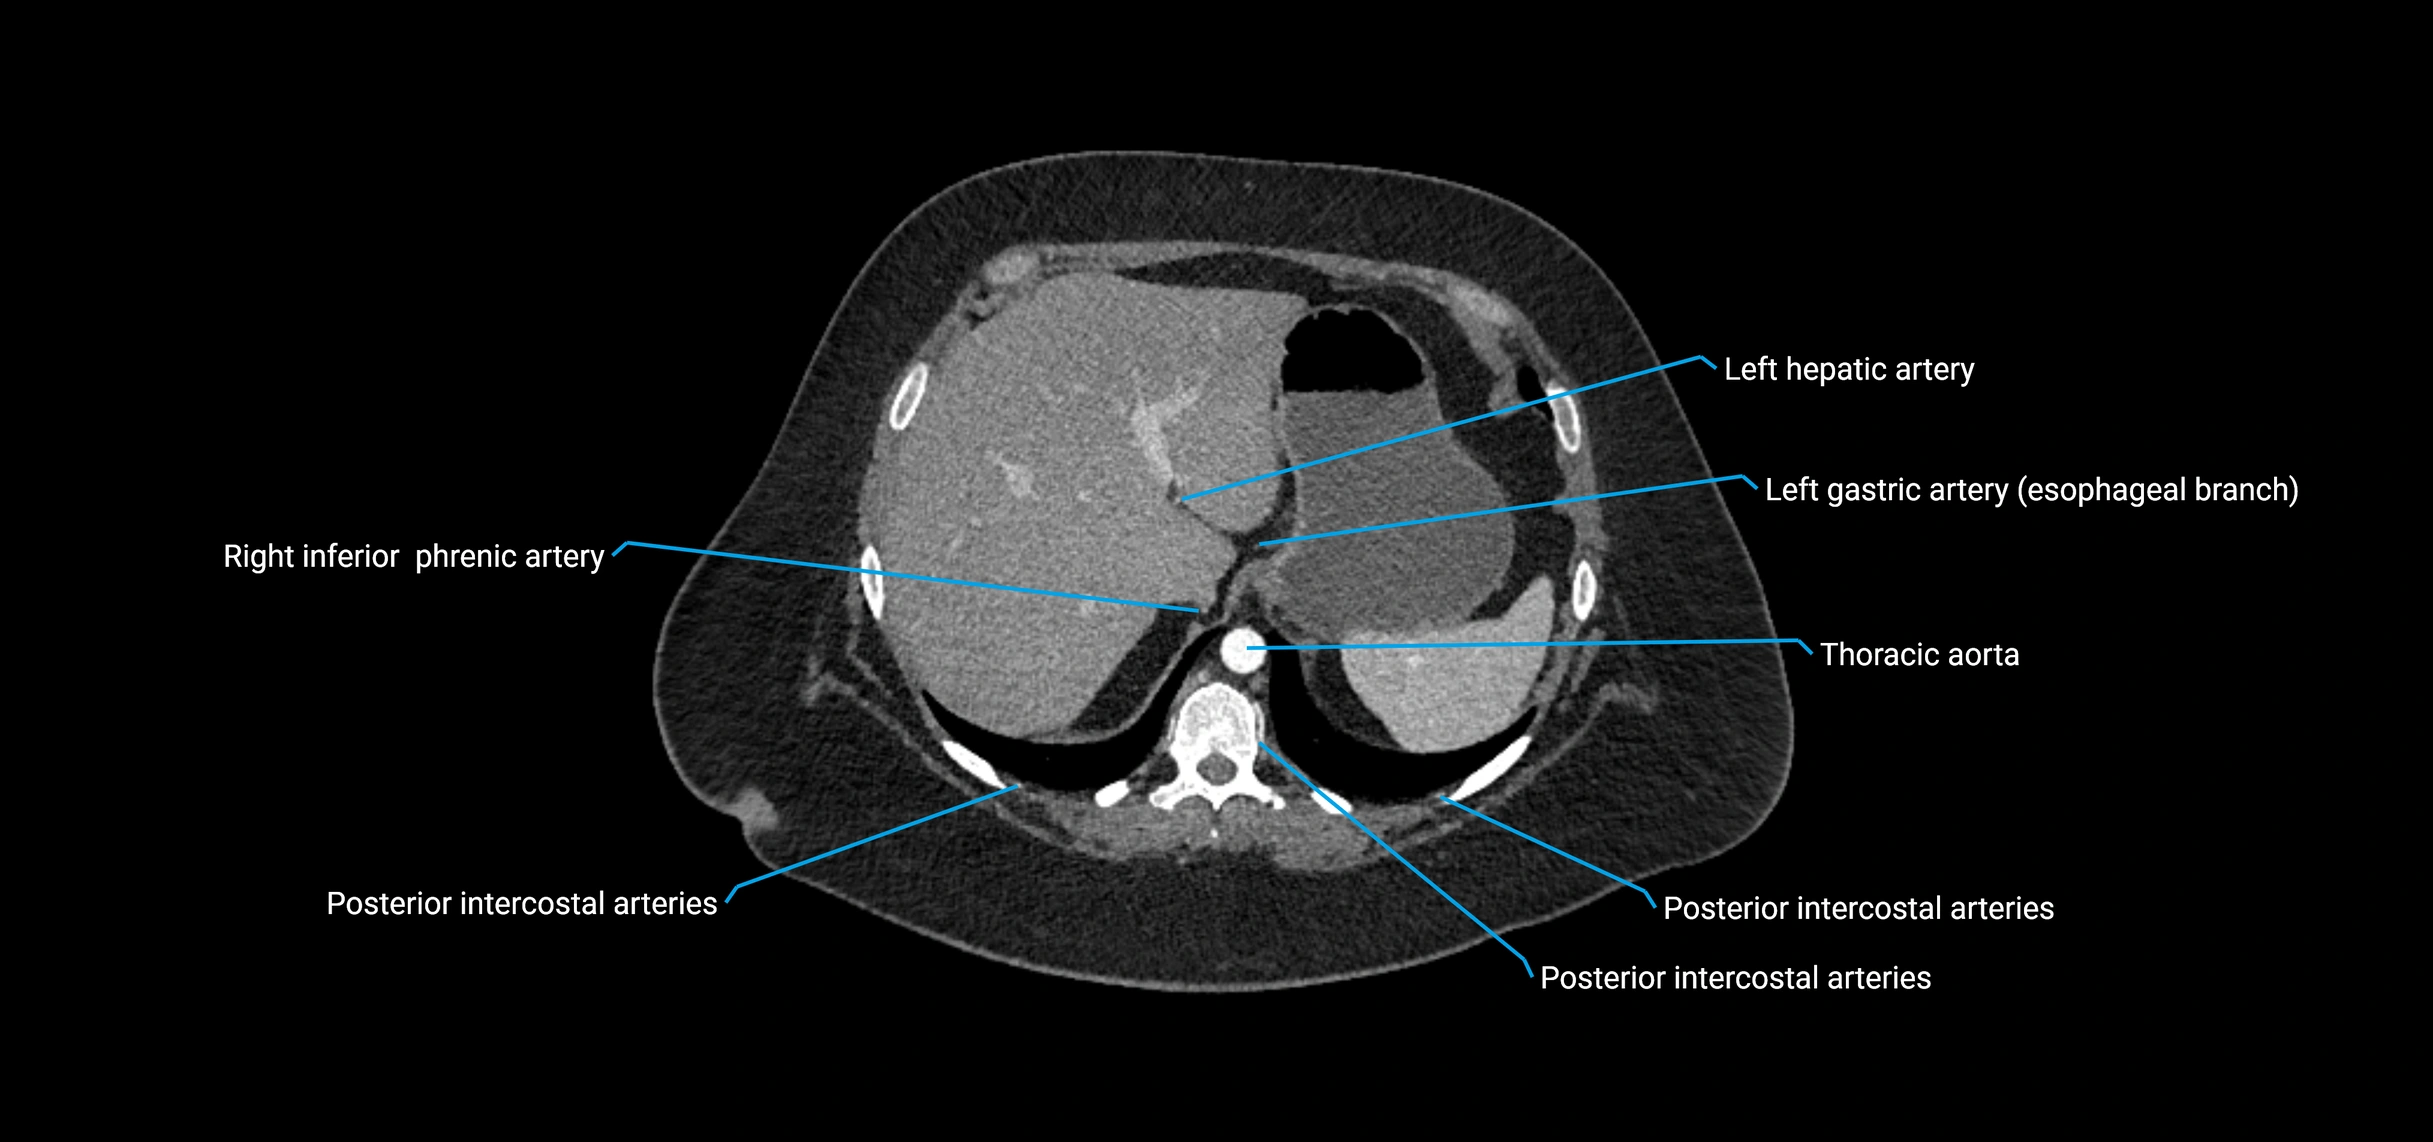

CT images

image